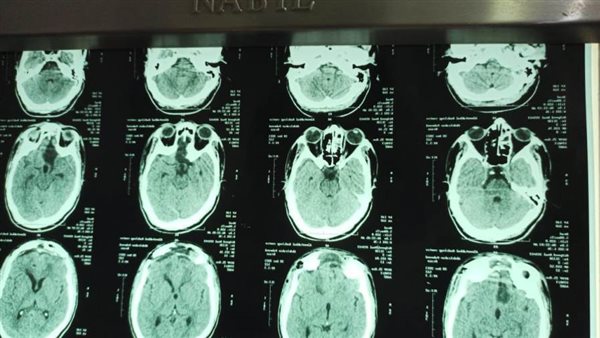

وأضاف الدكتور خالد عبدالعال المدير التنفيذي للمستشفيات الجامعية، أنه عقب استقبال المريض بالمستشفي تم عمل التحاليل والاشاعات والفحوصات اللازمة له، وذلك للوقوف علي مدي استعداده لإجراء العملية الجراحية، وتم اجراء العملية بواسطة فريق طبي متمكن في تلك الجراحات المتخصصة وتكللت جميع الجهود بالنجاح الباهر.

وأوضح الدكتور مؤمن المأمون رئيس قسم جراحة المخ والأعصاب أن الورم الذي كان يعاني منه المريض يعد من أكبر الأورام حجماً في قاع الجمجمة، واستغرقت الجراحة اكثر من ٨ ساعات، تمت خلالها استئصال كلى للورم، وتتم المتابعة الدورية له بالعيادة الخارجية بقسم جراحة المخ والاعصاب.